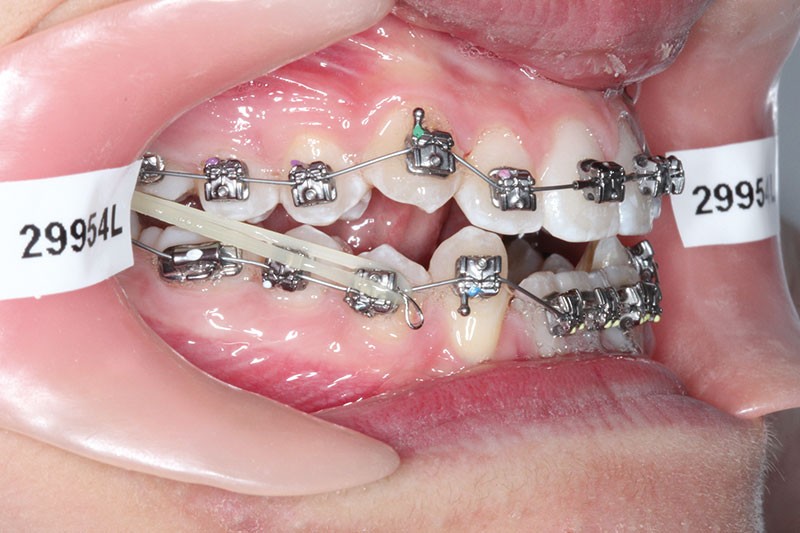

2e phase : mise en place du système multibague Carriere SLX (fig. 7 à 9)

Nous continuons le port des élastiques…